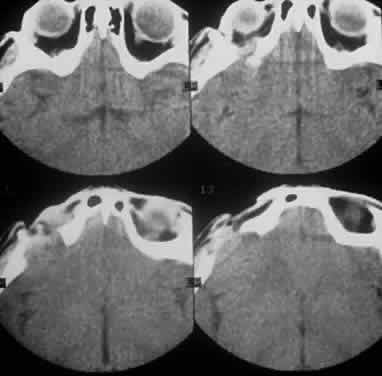

Computed tomography (CT) accurately demonstrates the molding of the mass to orbital structures, such as the globe and orbital bones, without bony erosion except in large cell lymphoma (Fig. 7). CT is used to localize the lesion, which tends to be unilateral and in both the intraconal and extraconal spaces. Lesions limited to the conjunctiva tend to be more benign with a better long-term prognosis, whereas those that extend into the orbit tend to be more malignant. Conjunctival lesions remain localized in 90% of cases, whereas orbital and lid lesions have a higher rate of systemic extranodal involvement.63 Lymphoid lesions of the lacrimal gland appear as a diffuse vertical expansion of the gland, which mold to both the globe and orbital bone without producing a bony fossa or erosion64 (Fig. 8). If the lesion extends beyond the orbital rim, the palpebral lobe of the gland is involved, and posterior or orbital lobe involvement appears as a straight line against orbital fat. Pleomorphic adenoma, on the other hand, appears as an oval, globular lesion with, in 80% of cases, adjacent bone changes caused by the firmer stroma of the tumor. Because epithelial tumors usually arise in the orbital lobe, extension beyond the orbital rim is not a feature.65 CT scan cannot distinguish between inflammatory and lymphoid lesions, because both lesions are homogeneous and enhance with intravenous contrast, and at biopsy, orbital lymphoid lesions are pink with a friable texture caused by the absence of stroma.66–68 The subtype and malignancy of the lesion can only be determined morphologically. The following subtypes of B-cell nonHodgkin's malignant lymphoma—extranodal B-cell marginal zone lymphoma, follicle center cell lymphoma, small lymphocytic lymphoma, lymphoplasmacytoid lymphoma, mantle cell lymphoma, large cell lymphoma, and Burkitt's lymphoma—are discussed in the approximate order of frequency with which they occur in the orbit.

Fig. 8. A CT scan, axial view, of a B-cell lymphoma localized to the anterior orbit bilaterally, with left lacrimal gland involvement and a normal adjacent lateral wall.